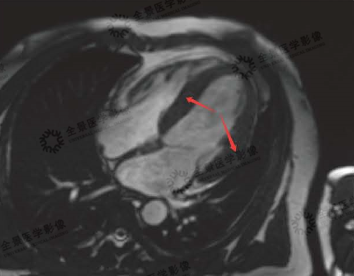

▲电影序列

红色箭头:非对称性增厚的心肌

黄色箭头:正常心肌

绿色箭头:二尖瓣反流血流信号

▲延迟强化序列

红色箭头:部分因为损伤纤维化的心肌

磁共振显示:心肌为非对称性肥厚,且部分心肌伴有纤维化表现,该患者为非对称性肥厚型心肌病。